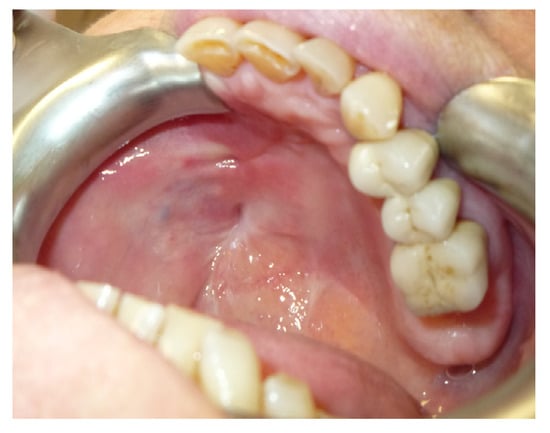

3.1.2. Case 2: P.S.

| P.S. | X | * | 7 | 0 | ||